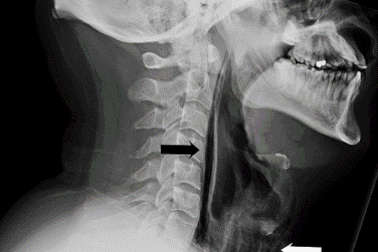

Kiềm chế hắt hơi có thể làm vỡ cổ họng, thủng màng nhĩKiềm chế cơn hắt hơi có thể làm vỡ cổ họng, thủng màng nhĩ hoặc làm vỡ mạch máu trong não của bạn. Đó là lời cảnh báo được các bác sĩ đưa ra trong một nghiên cứu đăng trên tạp chí y khoa BMJ Case Reports số ra mới đây.

Người đàn ông bị rách khí quản vì cố nhịn hắt hơiMột người đàn ông ngoài 30 tuổi tại thành phố Dundee (Scotland) vừa trải qua một trải nghiệm suýt mất mạng khi cố nhịn cơn hắt hơi trong lúc đang lái xe.